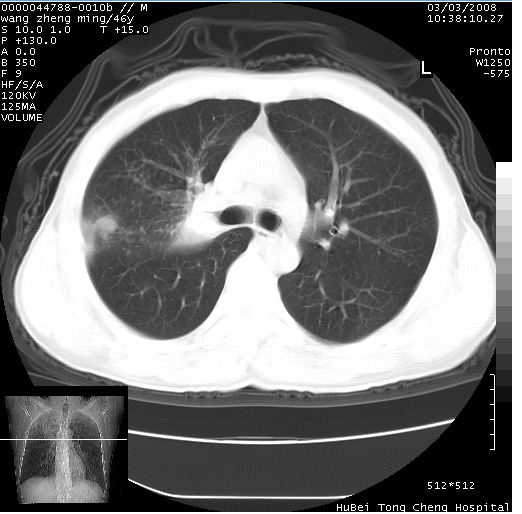

以下是引用卜一在2008-3-22 1:37:00的发言:[br]右肺实质性肿块,边缘不整,明显见毛刺征 分叶征及胸膜凹陷征,右上叶支气管明显变窄,远端散在的片状 斑片状实变影。另:左肺门较大肿块,支气管受累 变窄,远侧见阻塞性肺炎。纵隔内见肿大淋巴结。多考虑:右肺周围性肺癌伴左肺门 纵隔淋巴结转移!